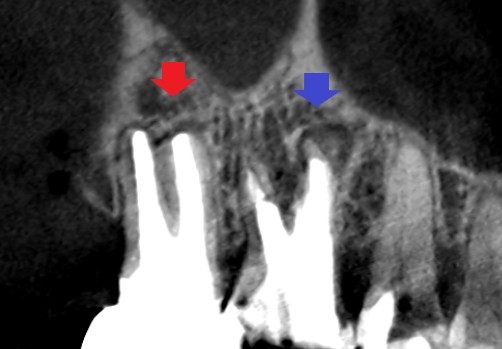

赤い矢印の先に大きな膿の影がみられます。膿の中には白い根管充填材らしい物質(青い矢印の先)の存在が確認されます。根管充填材を足掛かりにして細菌が繁殖している可能性があります。

再根管治療12ヶ月後のCT画像です。第一大臼歯は精密再根管治療のみ、第二大臼歯は精密再根管治療で改善がみられなかったため、歯根尖切除術を行いました。第一大臼歯、第二大臼歯共に膿の影の縮小と歯槽骨の再生がみられます。